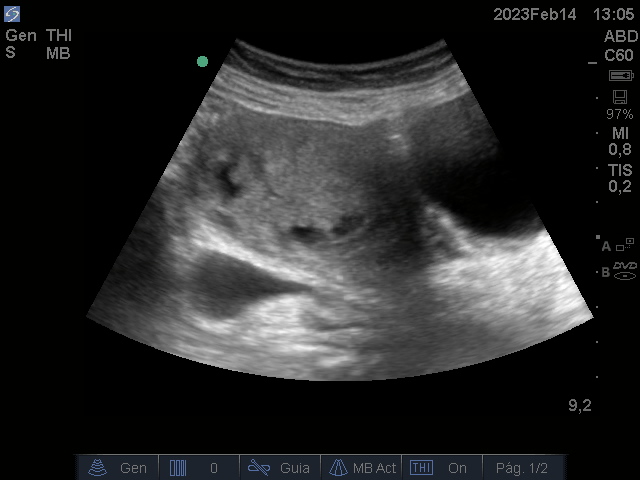

Se realiza ecografía renal y vesical en Consulta de médico de Cabecera

Hallazgos ecográficos

Útero aumentado de tamaño heterogéneo, con áreas sólido quísticas de bordes irregulares.